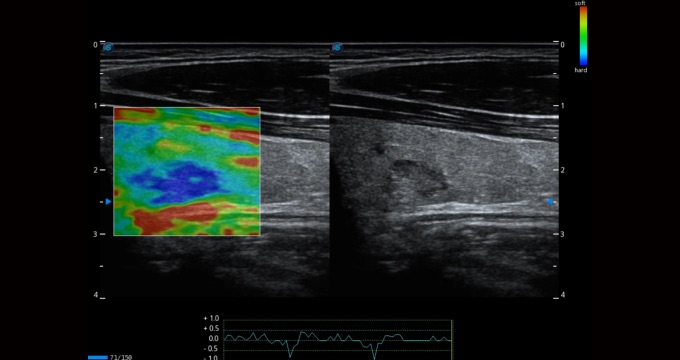

• Imágenes C-xlasto

Las imágenes C-xlasto permiten un análisis elástico cuantitativo completo, y el sistema calculará rápidamente la tasa de deformación y mostrará anomalías inusualmente duras o blandas dentro del tejido blando. Además, se apoya en múltiples sondas para garantizar una buena replicabilidad y resultados elásticos cuantitativos altamente constantes.

Arteria carótida